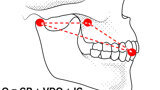

Fig. 2: Mandibular position with condyles down the eminence and maximal intercuspation.

Fig. 5: Occlusion represented as mandibular position and intercuspation.